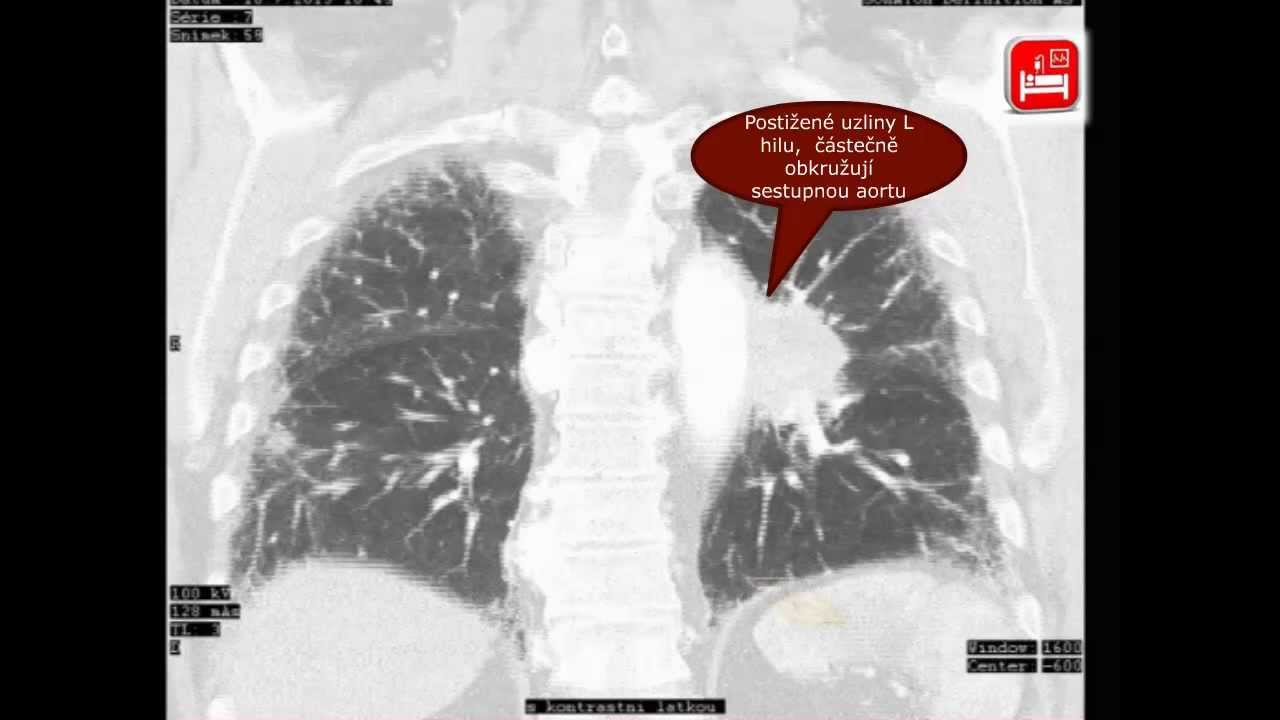

Plicní komplikace malobuněčného karcinomu plic – kazuistika